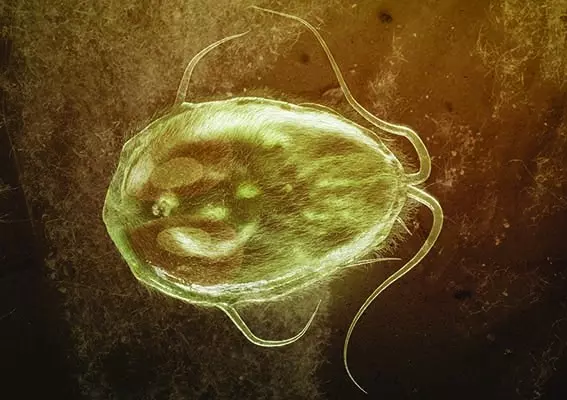

W grudniowym wydaniu czasopisma Naruroterapia w Praktyce poruszamy temat odporności zimą. Okres zimowy – pomimo bardzo efektownej otoczki i scenerii – jest tak naprawdę czasem niezwykle podstępnym, a to za sprawą złudzeń i wrażeń. Wprawdzie już pod koniec grudnia wymieniamy kalendarze wiszące na naszych ścianach i składamy sobie i bliskim wiele obietnic dotyczących zdrowia, ale tak naprawdę nie ma tu niczego innego oprócz sposobu zapisu daty. Nasze ciało z chwilą wybicia Nowego Roku nie staje się ani odrobinę nowsze, a układy i organy wcale nie działają lepiej. Z pewnością w umyśle mogą występować pewne przesilenia, przez co z impetem wkraczamy w początek miesiąca, ale wraz z pierwszą prozaiczną infekcją – jakich wiele w tym sezonie – wytracamy pęd i wszystko wraca w stare koleiny. Dlatego dobra odporność to skarb, albowiem ma na nas rzeczywisty i korzystny wpływ – pozwala się zmienić nie do poznania! Jak wzmocnić swoją odporność? Jakie produkty warto spożywać? Zapraszamy do lektury!